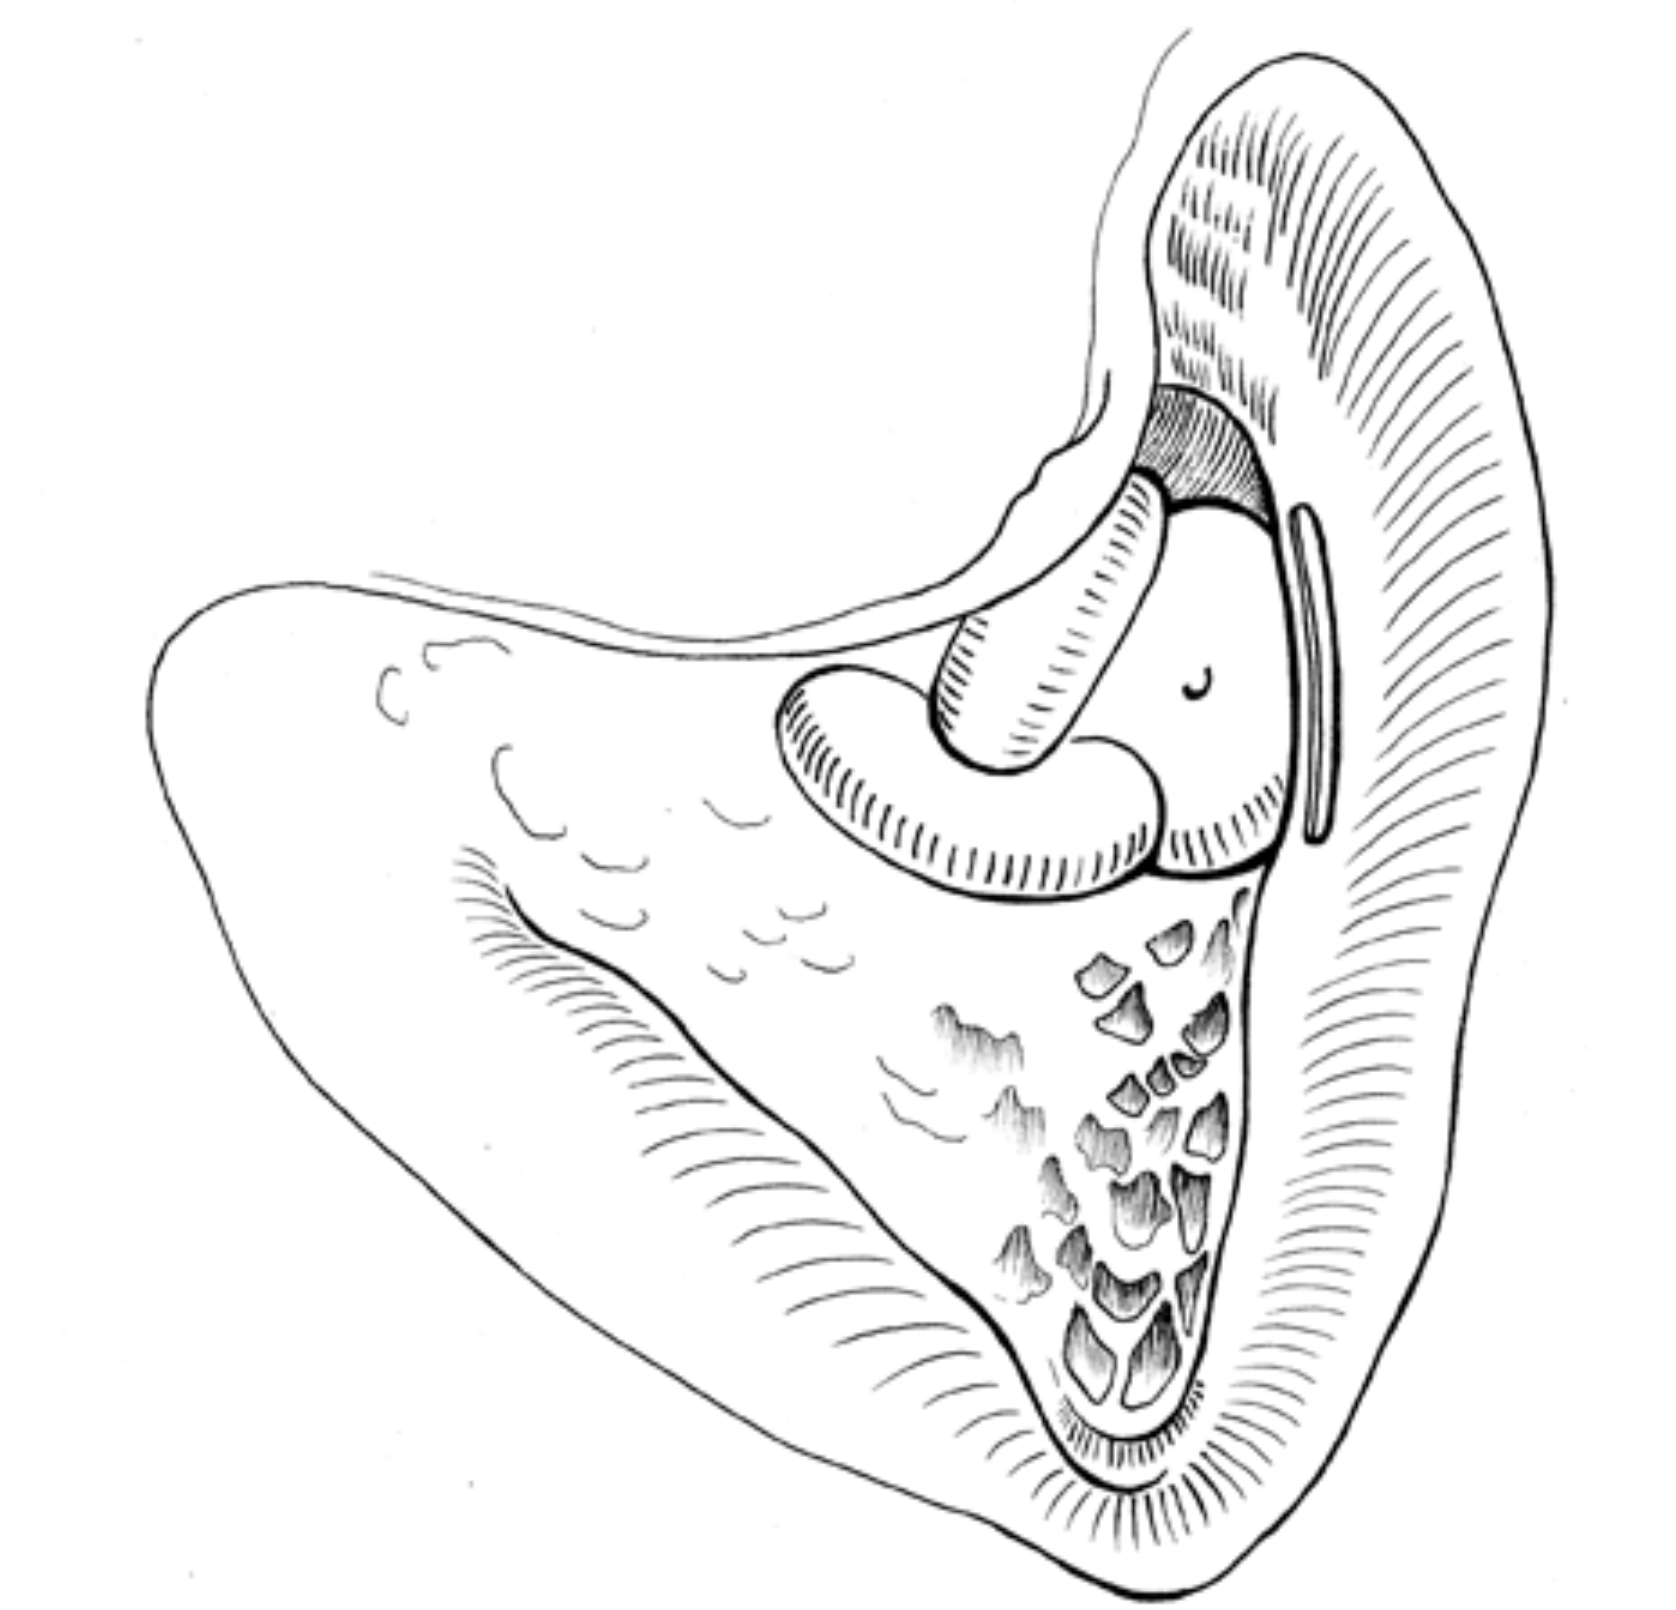

Advanced otology encompasses complex ear and skull base conditions requiring specialized surgical care. We offer cochlear implants and bone conduction implants for hearing loss, treat acoustic neuroma and temporal bone tumors, and perform stapes surgery for otosclerosis. Our team also manages cholesteatoma, superior canal dehiscence, and other advanced ear conditions. Select a topic below to learn more.